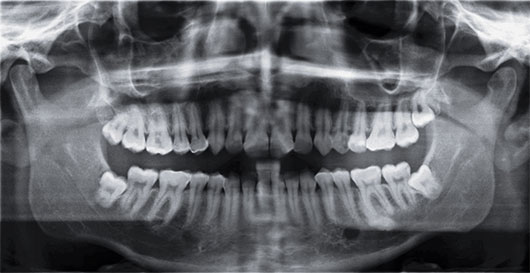

7. 아래 사진의 경우 사랑니가 신경관과 가까이 있어 신경손상의 위험이 높아 주의하여 발치해야 합니다.